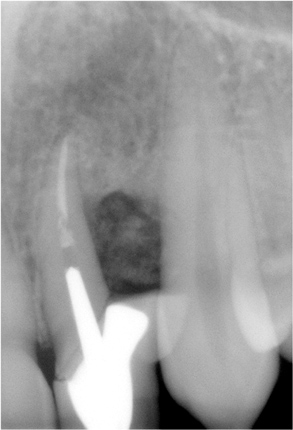

A single crown was designed with gingival ceramics onto the papilla site to solve the esthetic problem that clearly existed for her (Figure 10 and Figure 11).10 The treatment solution, as evidenced in the postoperative radiograph (Figure 12), kept the other treatment options open in the event of recurrent disease for the lateral incisor.

Figure 12 The postoperative radiograph evidences the persistence of the bone loss and the prosthetic solution.

Figure 12